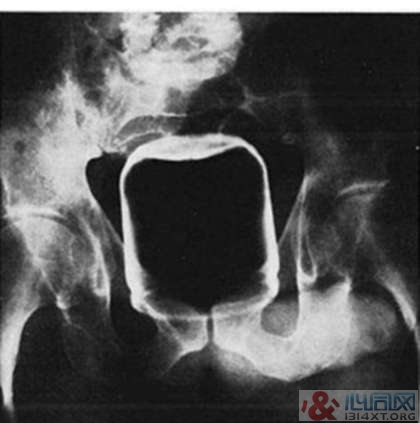

4. 装花生酱的罐子